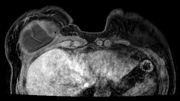

Standardized body region labelling of individual images provides data that can improve human and computer use of medical images. A CNN-based classifier was developed to identify body regions in CT and MRI. 17 CT (18 MRI) body regions covering the entire human body were defined for the classification task. Three retrospective databases were built for the AI model training, validation, and testing, with a balanced distribution of studies per body region. The test databases originated from a different healthcare network. Accuracy, recall and precision of the classifier was evaluated for patient age, patient gender, institution, scanner manufacturer, contrast, slice thickness, MRI sequence, and CT kernel. The data included a retrospective cohort of 2,934 anonymized CT cases (training: 1,804 studies, validation: 602 studies, test: 528 studies) and 3,185 anonymized MRI cases (training: 1,911 studies, validation: 636 studies, test: 638 studies). 27 institutions from primary care hospitals, community hospitals and imaging centers contributed to the test datasets. The data included cases of all genders in equal proportions and subjects aged from a few months old to +90 years old. An image-level prediction accuracy of 91.9% (90.2 - 92.1) for CT, and 94.2% (92.0 - 95.6) for MRI was achieved. The classification results were robust across all body regions and confounding factors. Due to limited data, performance results for subjects under 10 years-old could not be reliably evaluated. We show that deep learning models can classify CT and MRI images by body region including lower and upper extremities with high accuracy.

翻译:个人图像标准化体格标签提供了可以改进人体和计算机医疗图像使用的数据; 开发了一个CNN的分类器,以确定CT和MRI的人体区域; 为分类任务确定了覆盖整个人体的17个CT(18MRI)机构区域; 为AI模型培训、验证和测试建立了三个追溯数据库,每个机构区域的研究分布均衡; 测试数据库来自不同的保健网络; 对病人年龄、病人性别、机构、扫描机制造商、对比、切片厚度、MRI序列和CT内核的分类器进行了准确、回顾和精确性评价; 数据包括2 934个匿名CT案例的追溯组(培训:1 804项研究、验证:602项研究、测试:528项研究)和3 185个匿名MRI案例(培训:1 911项研究、验证:636项研究、测试:638项研究)。 初级护理医院、社区医院和成像中心27个机构对测试数据集进行了准确性评估; 数据包括:92%以上的性别比例和科目的追溯性案例; 95年的高级和90个高等级数据序列,显示为91至90区域。